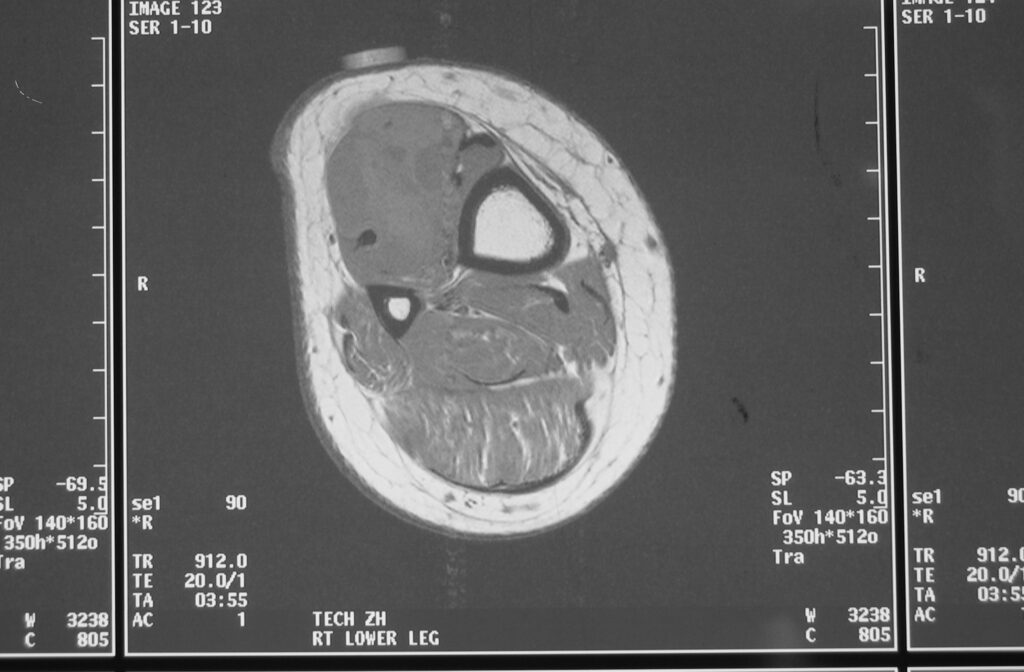

MRI

Shows multiloculated, heterogeneous mass.

“Triple Signal Intensity sign”; hypointense, isointense and hyperintense with fat on T2 – weighted MRI imaging. This sign is present in 30 to 50% of the cases. (Fig.3)

Under contrast enhancement Synovial Sarcoma appears heterogeneous and demonstrate areas of nodular enhancement.

In approximately 30% of cases a multiple vascular cannel may be identified

Synovial sarcomas may have a cystic appearance and are often mistaken for ganglion cysts especially those adjacent to tendons and in the foot and ankle.